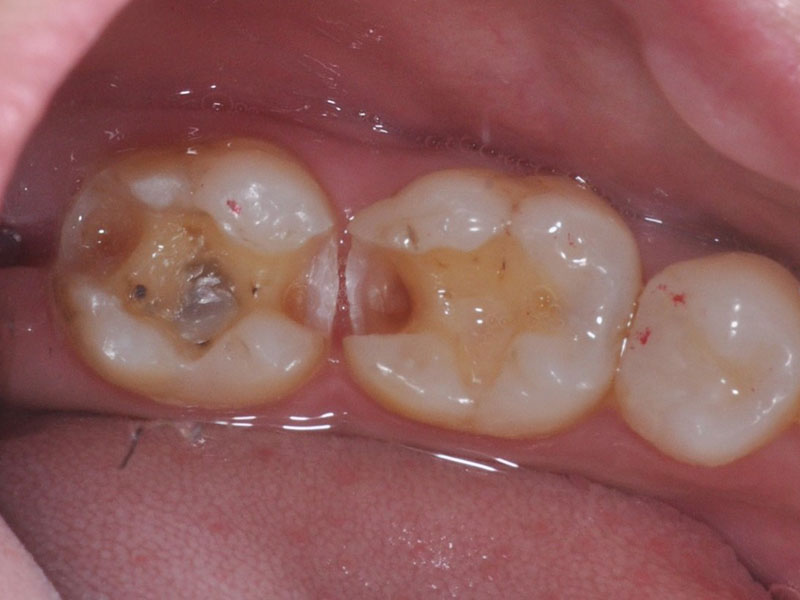

治療前